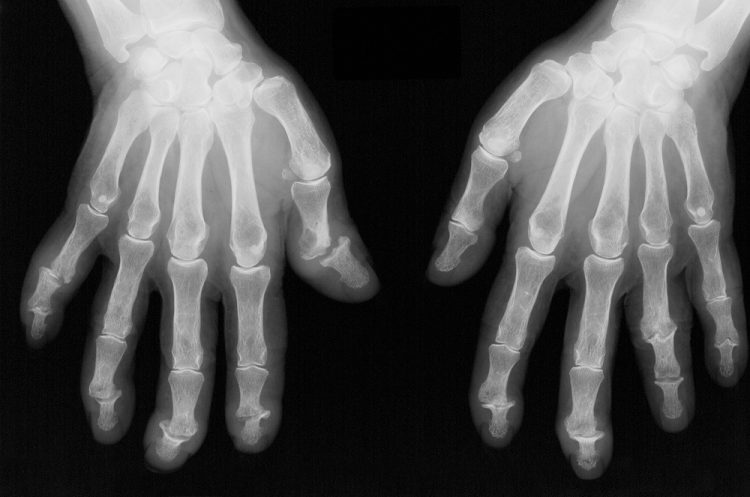

The burden of bone damage and trabecular bone loss at the

metacarpal heads is higher among patients with psoriatic arthritis (PsA)

compared with healthy controls, according to study results published in Osteoporosis International.1

Previous studies have showed that inflammatory PsA may cause

structural damage at the metacarpophalangeal joint, which makes the metacarpal

heads vulnerable to inflammation and bone loss in patients with PsA.2